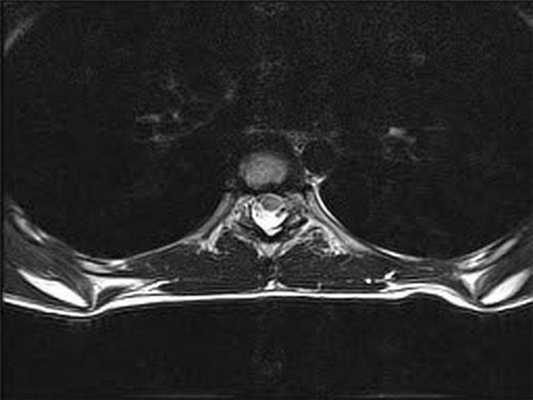

Менингиома на снимке МРТ грудного отдела позвоночника в аксиальной проекции

МРТ грудного отдела позвоночника в аксиальной проекции

Менингиома грудного отдела позвоночника на МРТ, постконтрастное изображение